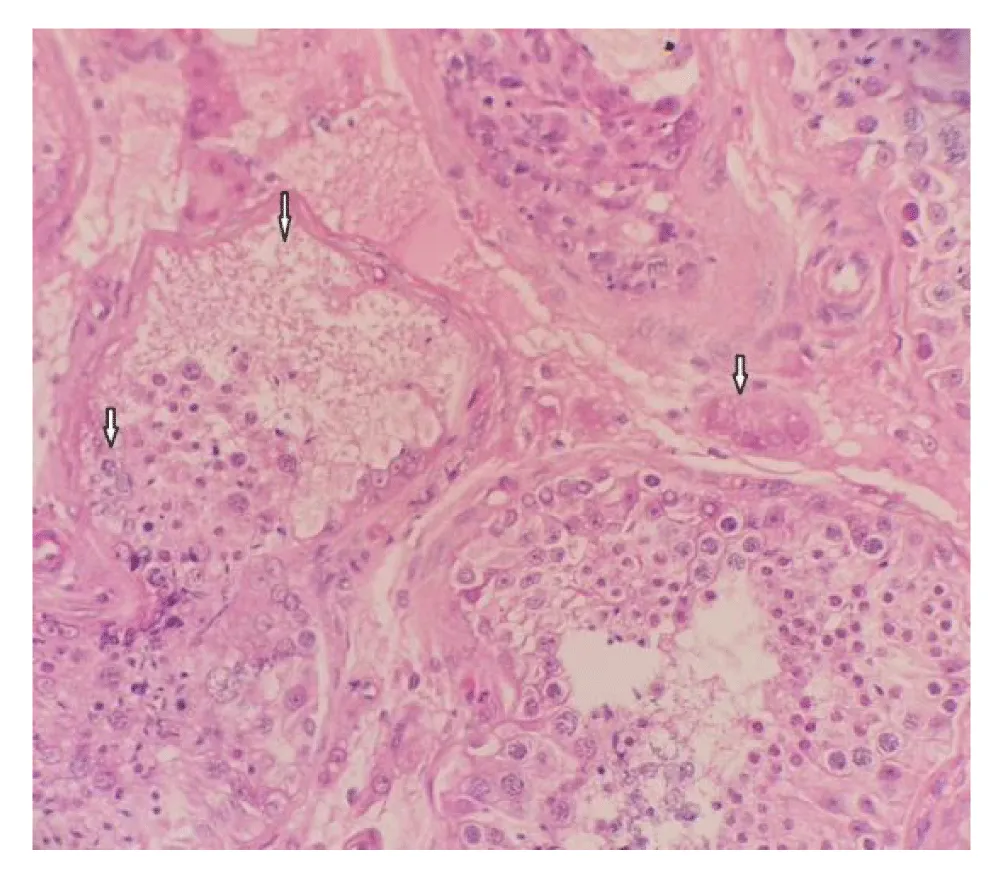

A 17-year-old boy was referred to the Clinic on February 11, 2025, due to pain and swelling of the left testicle. The swelling and pain have been present for the past 9 hours. He denies any trauma. Physical examination: The skin of both testes is normal in colour; the cremasteric reflex is absent. The left testis is palpably tender to palpation in the transverse position. An urgent testicular ultrasound with Color Doppler analysis and laboratory tests was performed. The ultrasound showed a whirlpool sign of the left spermatic cord, with an edematous epididymis. Color Doppler analysis revealed no detectable vascularization. A small hydrocele and edema of the soft tissues of the left hemiscrotum were also observed. Inflammatory markers and laboratory results are within normal limits. Surgical intervention is indicated based on suspicion of torsion of the left testis. Under general anesthesia, a transverse incision was made to access the testis, which was found to be softer in consistency and intravaginally twisted 540 degrees (Figure 1,2). Testicular viability was preserved; therefore, it was decided to retain and fixate the testis. A testicular biopsy was taken during the surgery. Testicular biopsy pathohistologically showed preserved seminiferous tubules with preserved spermatogenesis. Congestion of blood vessels and mild interstitial edema were present. Incipient necrosis of individual cells was seen in two canaliculi (Figure 3). Anticoagulant therapy was initiated, along with antibiotic treatment using a cephalosporin and analgesics. Locally, cold compresses were applied. The early postoperative course was uneventful. The first follow-up is scheduled for 7 days—both testicles are in the scrotum, and the surgical wound is healing well. The next follow-up is planned in one month, including testicular ultrasound with volumetry and Color Doppler analysis. We did not perform bilateral orchidopexy in the same procedure because it is standard at our Clinic. Contralateral orchidopexy is planned to be performed after 3 months due to inflammatory changes in the affected testicle and surrounding tissue.